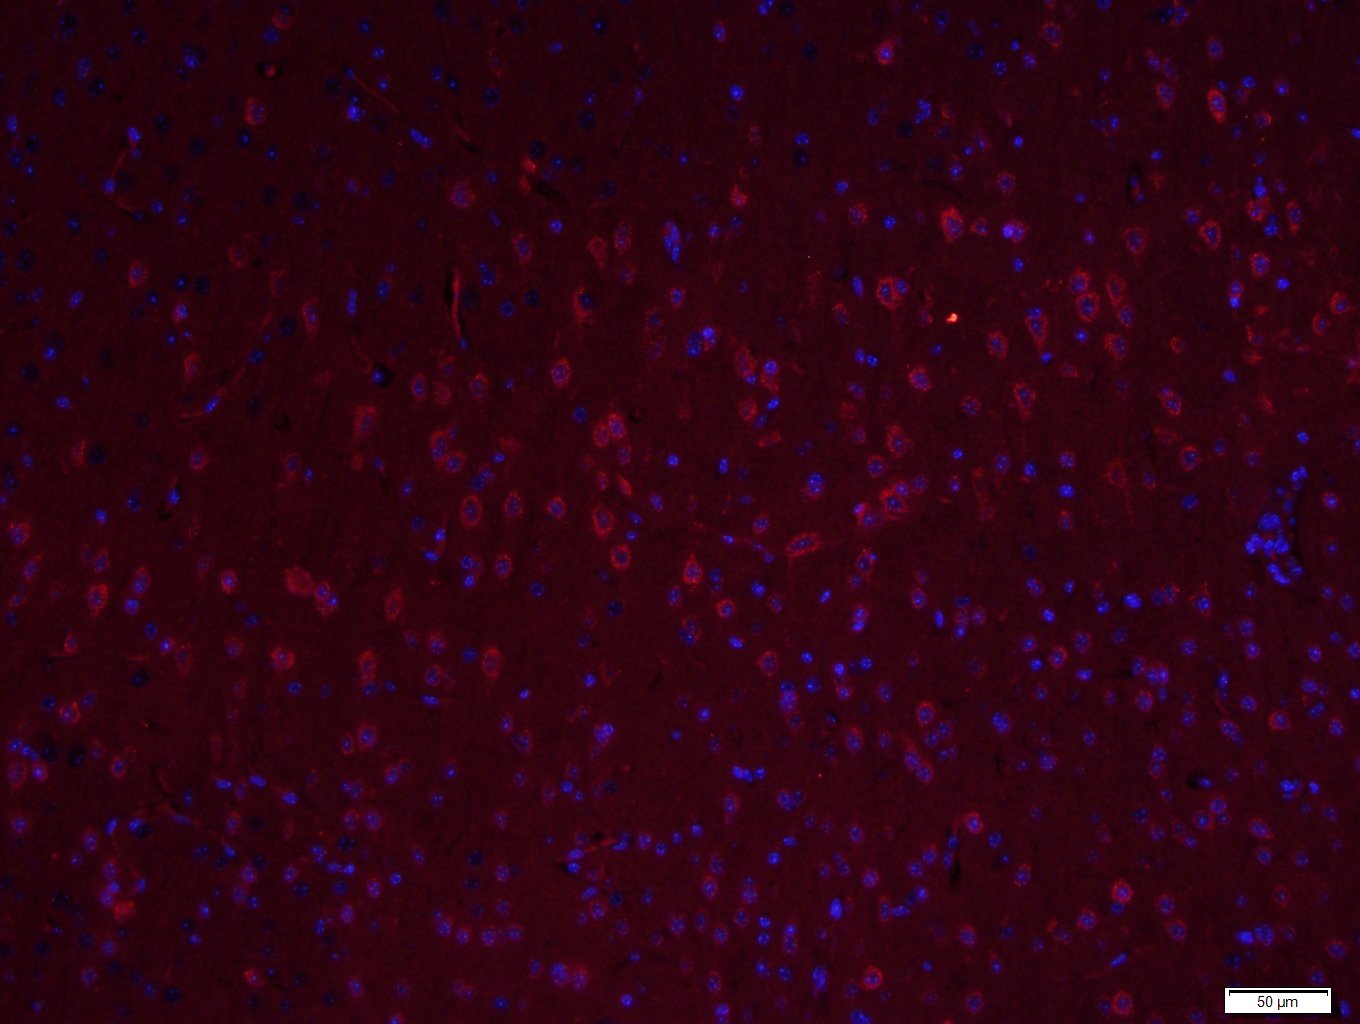

Paraformaldehyde-fixed, paraffin embedded (Rat brain); Antigen retrieval by boiling in sodium citrate buffer (pH6.0) for 15min; Block endogenous peroxidase by 3% hydrogen peroxide for 20 minutes; Blocking buffer (normal goat serum) at 37°C for 30min; Antibody incubation with (LIM kinase 1 + 2) Polyclonal Antibody, Unconjugated (bs-11871R) at 1:400 overnight at 4°C, followed by a conjugated Goat Anti-Rabbit IgG antibody (bs-0295G-CY3) for 90 minutes, and DAPI for nuclei staining.

Paraformaldehyde-fixed, paraffin embedded (Mouse brain); Antigen retrieval by boiling in sodium citrate buffer (pH6.0) for 15min; Block endogenous peroxidase by 3% hydrogen peroxide for 20 minutes; Blocking buffer (normal goat serum) at 37°C for 30min; Antibody incubation with (LIM kinase 1 + 2) Polyclonal Antibody, Unconjugated (bs-11871R) at 1:400 overnight at 4°C, followed by a conjugated Goat Anti-Rabbit IgG antibody (bs-0295G-CY3) for 90 minutes, and DAPI for nuclei staining.